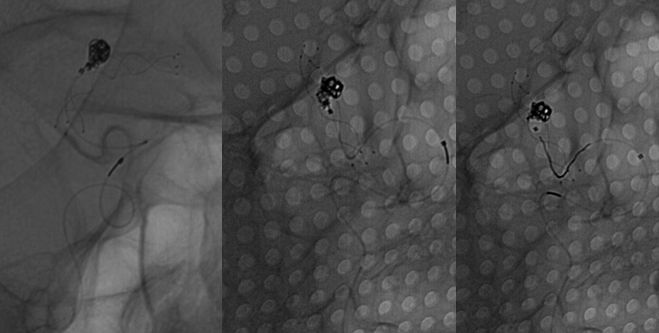

图4 Headway21及Headway17直头微导管到位,第一枚弹簧圈成篮

图5 Lvis支架释放

图6 最后一枚弹簧圈推送后更换角度见弹簧圈部分位于支架及血管壁之间,考虑对侧A1缺如,右侧A1重要,必须保留,撤出弹簧圈